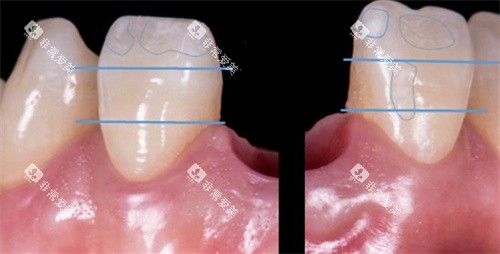

牙齿贴面修复(单颗):850元起

烤瓷牙冠:320元起

全瓷牙冠:1200元起